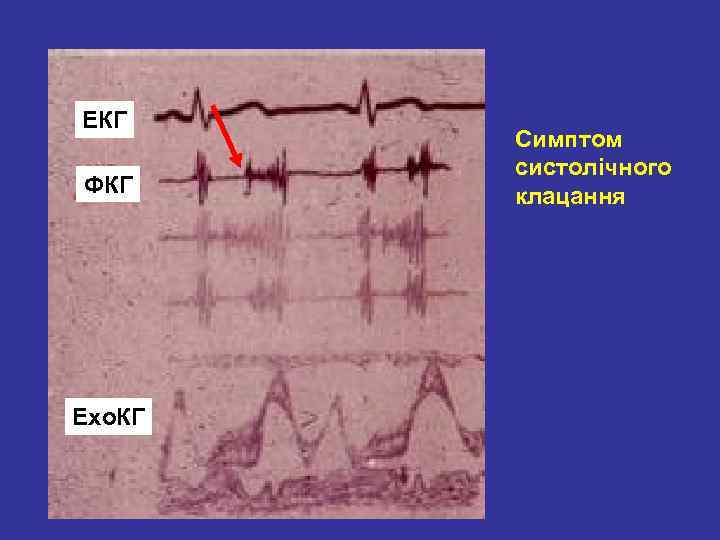

СИНДРОМ ПРОЛАБУВАННЯ КЛАПАНІВ СЕРЦЯ Скарги: • дискомфорт в ділянці серця, запаморочення, серцебиття, епізоди епритомності, колючий або тиснучий біль в грудній клітці, задишка, загальна слабість, відчуття страху смерті, порушення ритму При аускультації - систолічне клацання посередині систоли Двомірна Ехо. КГ: систолічне зміщення передньої (задньої) стулки в ліве передсердя, потовщення стулок МК, розширення мітрального кільця. Доплер- Ехо. КГ: регургітація через пролабуючий клапан в ліве передсердя та збільшення його діаметра

ЕКГ ФКГ Ехо. КГ Симптом систолічного клацання